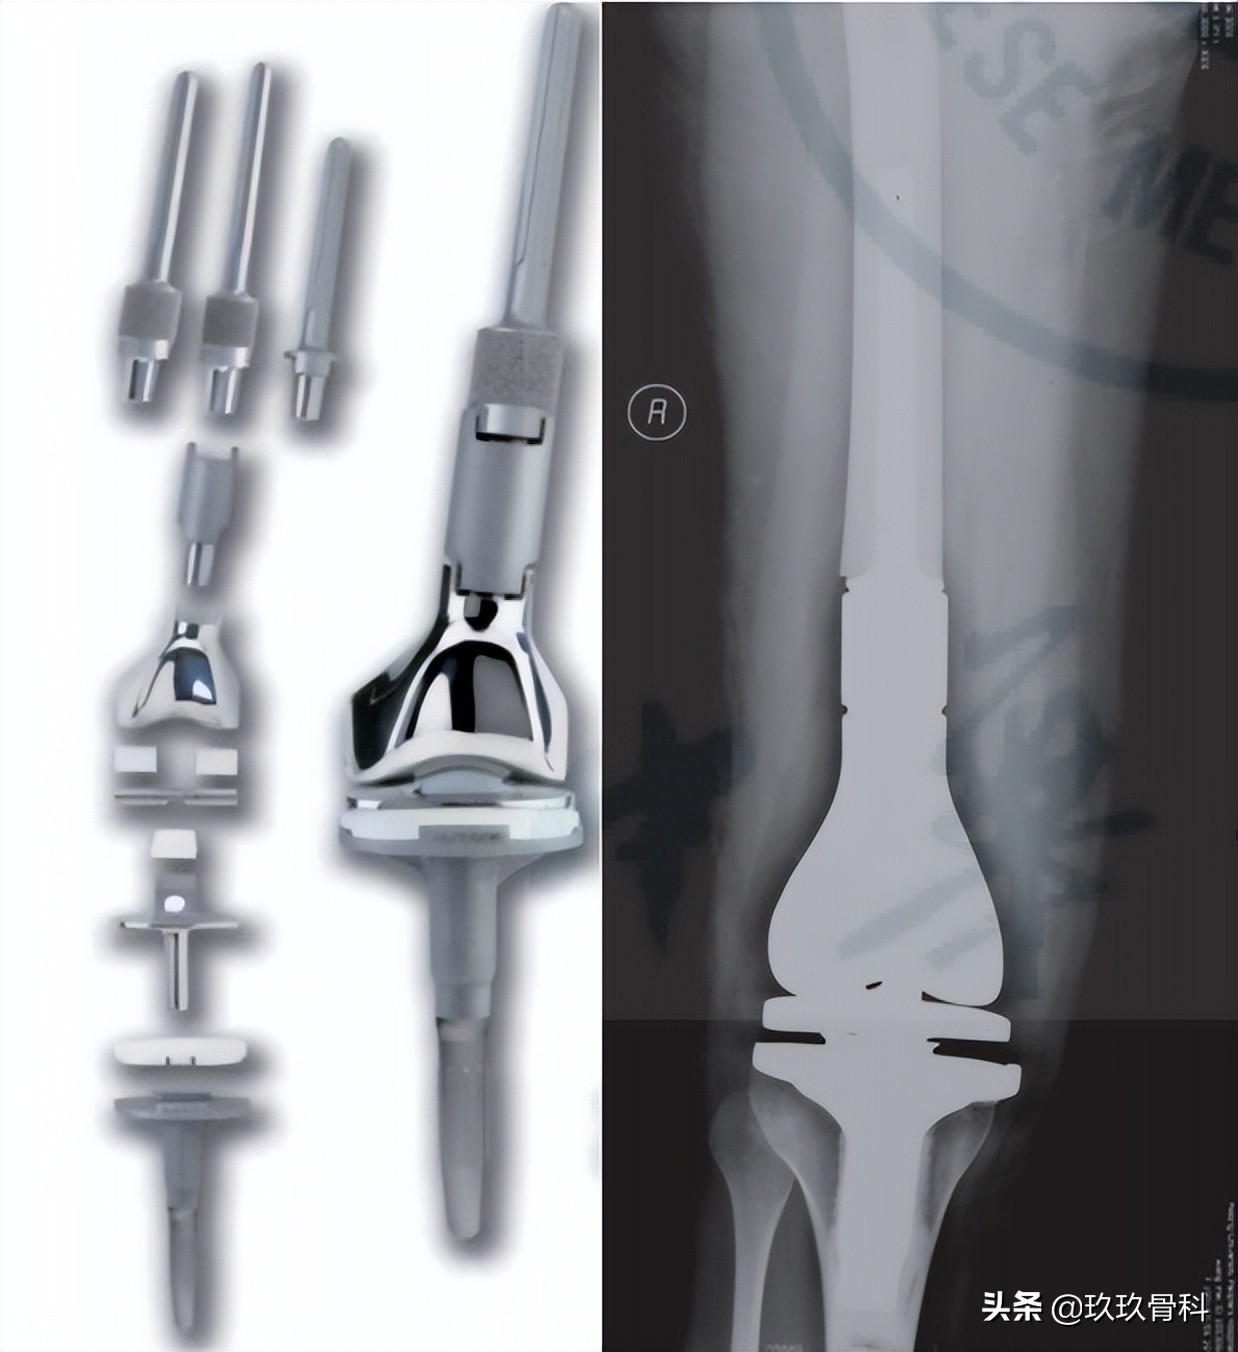

早期定制型膝关节假体多为单纯铰链型(simple hinge),即股骨和胫骨组件通过单一铰链轴连接,仅使膝关节在矢状面上做屈伸运动,重建膝关节的稳定性,但随访发现无菌性松动发生率较高。随着研究者对膝关节生物力学认识的逐渐深入,发现膝关节在屈伸运动时股骨和胫骨还伴有水平面的相对旋转运动。据此改进设计并出现了旋转铰链式肿瘤膝关节假体(rotating-hinge),该设计更加仿生,集中于假体柄-骨界面的大部分旋转力被旋转平台所吸收(图2)。

图2组配式旋转铰链型膝关节假体